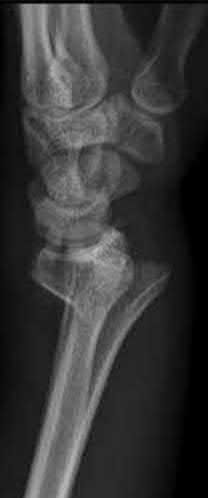

Question 6

A 22-year-old male falls onto an outstretched hand and sustains a displaced fracture through the proximal pole of the scaphoid. Avascular necrosis of the proximal pole is highly likely due to the disruption of its primary vascular supply. Which vessel provides this critical retrograde perfusion?

Explanation

The primary blood supply to the scaphoid is from the dorsal carpal branch of the radial artery, which enters the dorsal ridge of the scaphoid at the waist and courses proximally. This retrograde blood flow makes proximal pole fractures highly susceptible to avascular necrosis and nonunion. The superficial palmar branch provides a minor supply (about 20%) to the distal pole.